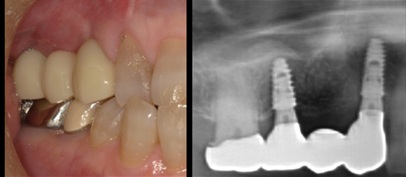

臼歯大きくGBR(骨造成)50代男性

治療前

治療後

施術名 | 抜歯GBR(骨造成)そーせじテクニック →インプラント埋入 |

主訴 | 噛めない |

施術の副作用(リスク) | 脱落感染 |

施術の価格 | 1本GBR5万~10万(税抜き)+インプラント埋入補綴まで35万(税抜き) FGG5万 ソケットリフト6万 |

コメント | 臼歯部はほとんど骨がなく垂直的に骨を作ってからインプラント埋入を行いました |